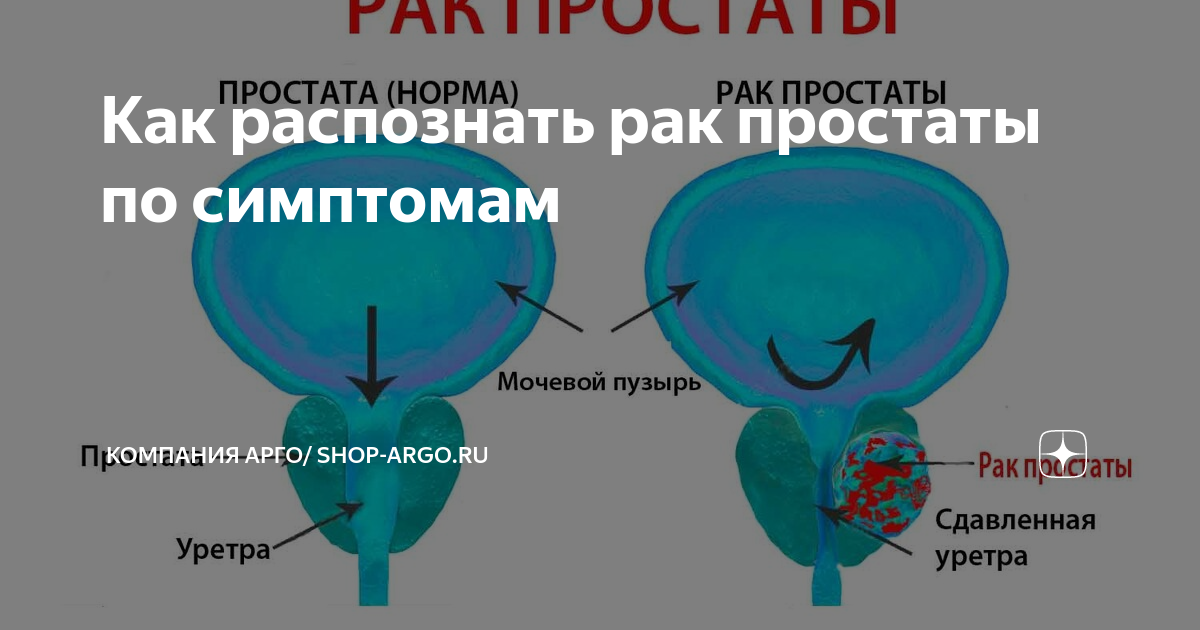

Предстательная железа 3д. Опухоль предстательной железы. Злокачественные новообразования простаты. Карцинома предстательной железы Карцинома предстательной железы. Что такое РПЖ предстательной железы. Онкология предстательной железы. Злокачественное новообразование предстательной железы

Карцинома предстательной железы. Что такое РПЖ предстательной железы. Онкология предстательной железы. Злокачественное новообразование предстательной железы Опухоль предстательной железы. Опухоль простаты симптомы. Злокачественное новообразование предстательной железы. Фиброз предстательной железы

Опухоль предстательной железы. Опухоль простаты симптомы. Злокачественное новообразование предстательной железы. Фиброз предстательной железы ТНМ классификация предстательной железы. Опухоли предстательной железы классификация. Классификация степени аденомы простаты. TNM предстательная железа

ТНМ классификация предстательной железы. Опухоли предстательной железы классификация. Классификация степени аденомы простаты. TNM предстательная железа Карцинома предстательной железы. Cancer предстательной железы. Раковые клетки простаты

Карцинома предстательной железы. Cancer предстательной железы. Раковые клетки простаты Онкология предстательной железы. Опухоль простаты симптомы. Карцинома предстательной железы

Онкология предстательной железы. Опухоль простаты симптомы. Карцинома предстательной железы Онкология предстательной железы. Предстательная железа презентация. Презентация онкология предстательной. Предстательная железа rak